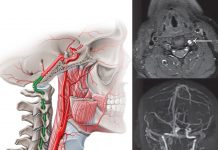

Hemorajik İnme (Stroke) Acil Yaklaşım

Hemorajik inme, serebrovasküler olayların yaklaşık %10–15’ini oluşturmasına rağmen en yüksek mortalite oranına sahip inme tipidir. Beyin parankimi içine (intraserebral kanama) veya subaraknoid aralığa (subaraknoid...